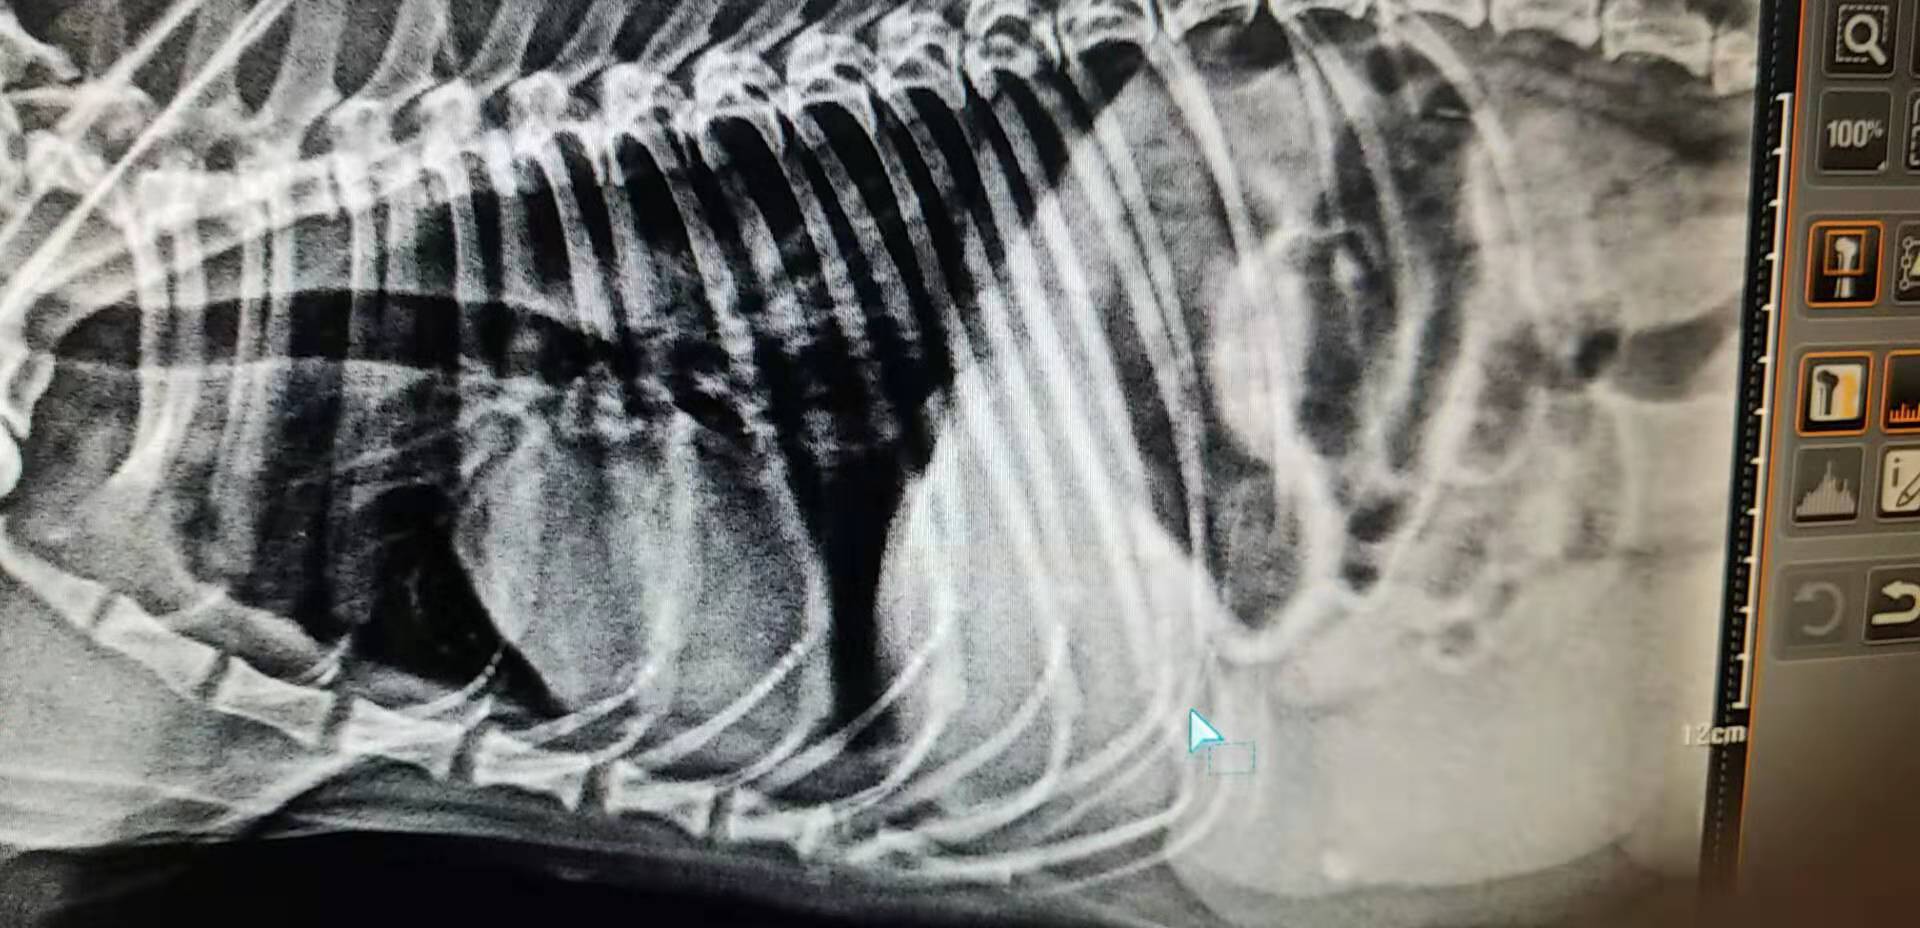

X光的摄片

一例犬的子宫蓄脓病例